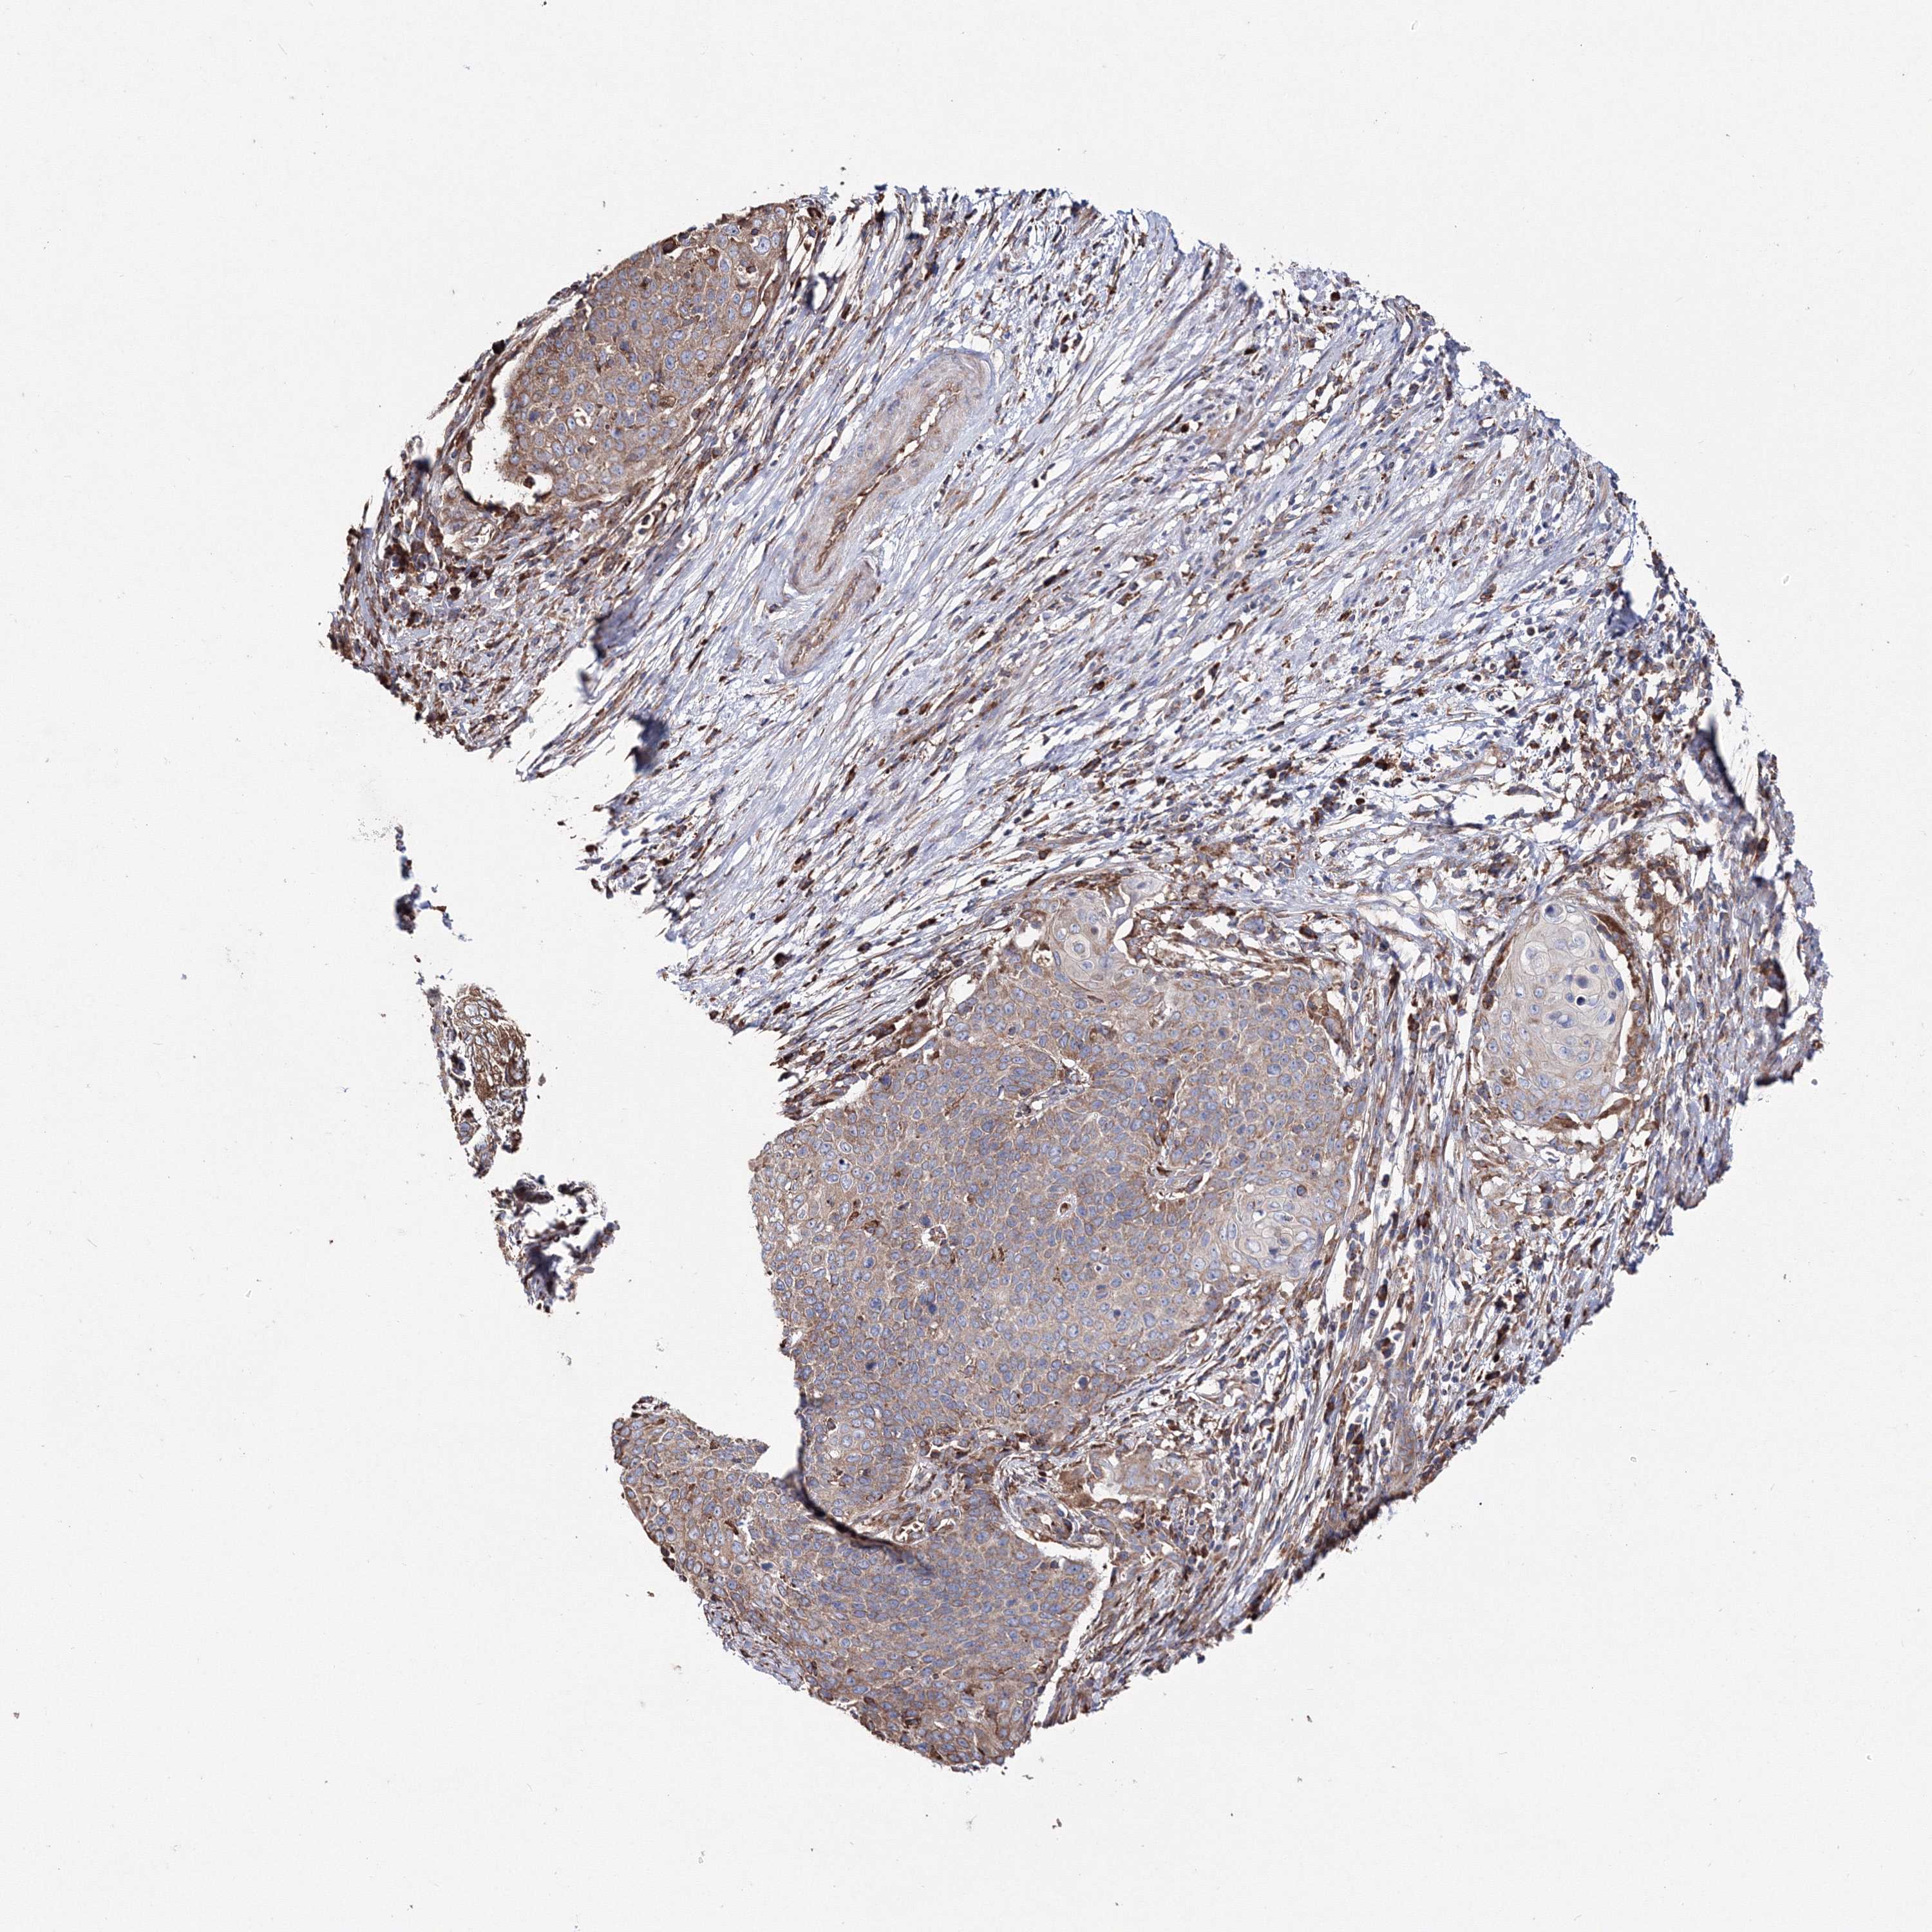

CERVICAL CANCER - Protein expressioni

A mouse-over function shows sample information and annotation data. Click on an image to view it in a full screen mode. Samples can be filtered based on level of antibody staining by selecting one or several of the following categories: high, medium, low and not detected. The assay and annotation is described here.

Note that samples used for immunohistochemistry by the Human Protein Atlas do not correspond to samples in the TCGA dataset.

Antibody stainingi

Antibody staining in the annotated cell types in the current human tissue is reported as not detected, low, medium, or high, based on conventional immunohistochemistry profiling in selected tissues. This score is based on the combination of the staining intensity and fraction of stained cells.

Each image is clickable and will lead to virtual microscopy that enables deeper exploration of all samples and also displays staining intensity scores, fraction scores and subcellular localization as well as patient and tissue information for each sample.

Antibody HPA036871

Staining

High

Medium

Low

Not detected

Intensity

Strong

Moderate

Weak

Negative

Quantity

>75%

75%-25%

<25%

None

Location

Nuclear

Cytoplasmic/membranous

Cytoplasmic/membranous,nuclear

Squamous cell carcinoma, NOS

Adenocarcinoma, NOS